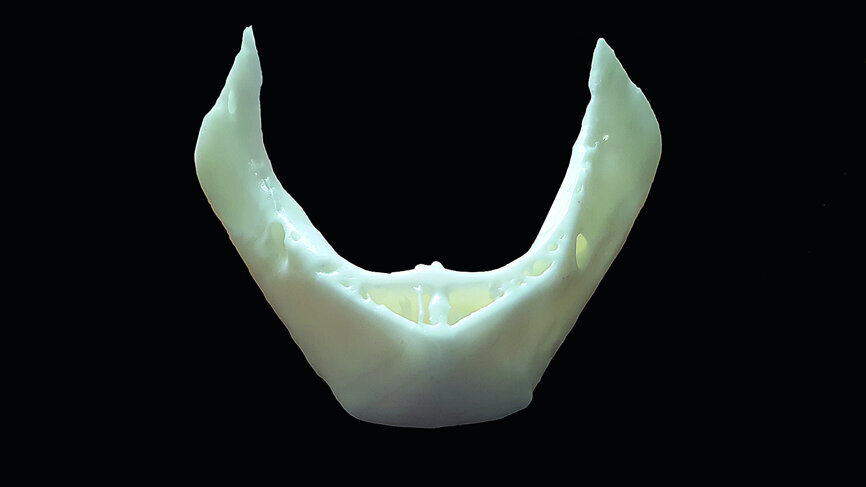

Fig. 12: The mandibular 3-D reconstructed volumes illustrating the hollow areas and potential implant receptor sites.

As technology becomes more available to clinicians worldwide, our ability to diagnose and plan with improved accuracy and consistency can only be seen as a huge benefit. The use of 3-D printing has now become an affordable option for both group practices and single practitioners, therefore making it possible to produce accuracy biomedical models that greatly enhance the diagnostic and treatment planning phase. DICOM data can be exported to standard files that can be managed in software that drives 3-D printers to fabricate models of the mandible or the maxilla. The CBCT dataset from the case presentation contained within this article was exported as a standard triangulation language (STL) file and imported into the 3-D printer software (PreForm Formlabs; Fig. 21).

The importance of having an actual model in hand cannot be underestimated. For this particular case presentation, the 3-D printed model was fabricated using a process known as stereolithography by an in-office 3-D printer, the Form 2 (Formlabs). The surface detail is excellent and provides not just an excellent diagnostic aid, but a method to educate our patients on the recommended treatment plan based on a physical model that can be viewed and touched. It has been demonstrated that these models can be successfully used for guided surgery applications, and for other bone grafting guides such as a ‘sinus-lift’ or ‘harvest’ guide. The virtual 3-D reconstructed surface model can be seen in Figure 22a, and the 3-D printed model in Figure 22b. The position of the bilateral mental foramina can be clearly seen, as well as the intramedullary bone within the ramus, and the anterior symphysis where the hollow areas were noted. These models can also be utilised to simulate the actual surgical approach to validate the procedure and for surgical guide fabrication.